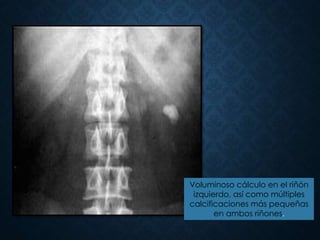

Voluminoso cálculo en el riñón

izquierdo, así como múltiples

calcificaciones más pequeñas

en ambos riñones.

Voluminoso cálculo enel riñón izquierdo, así como múltiples calcificaciones más pequeñas en ambos riñones.